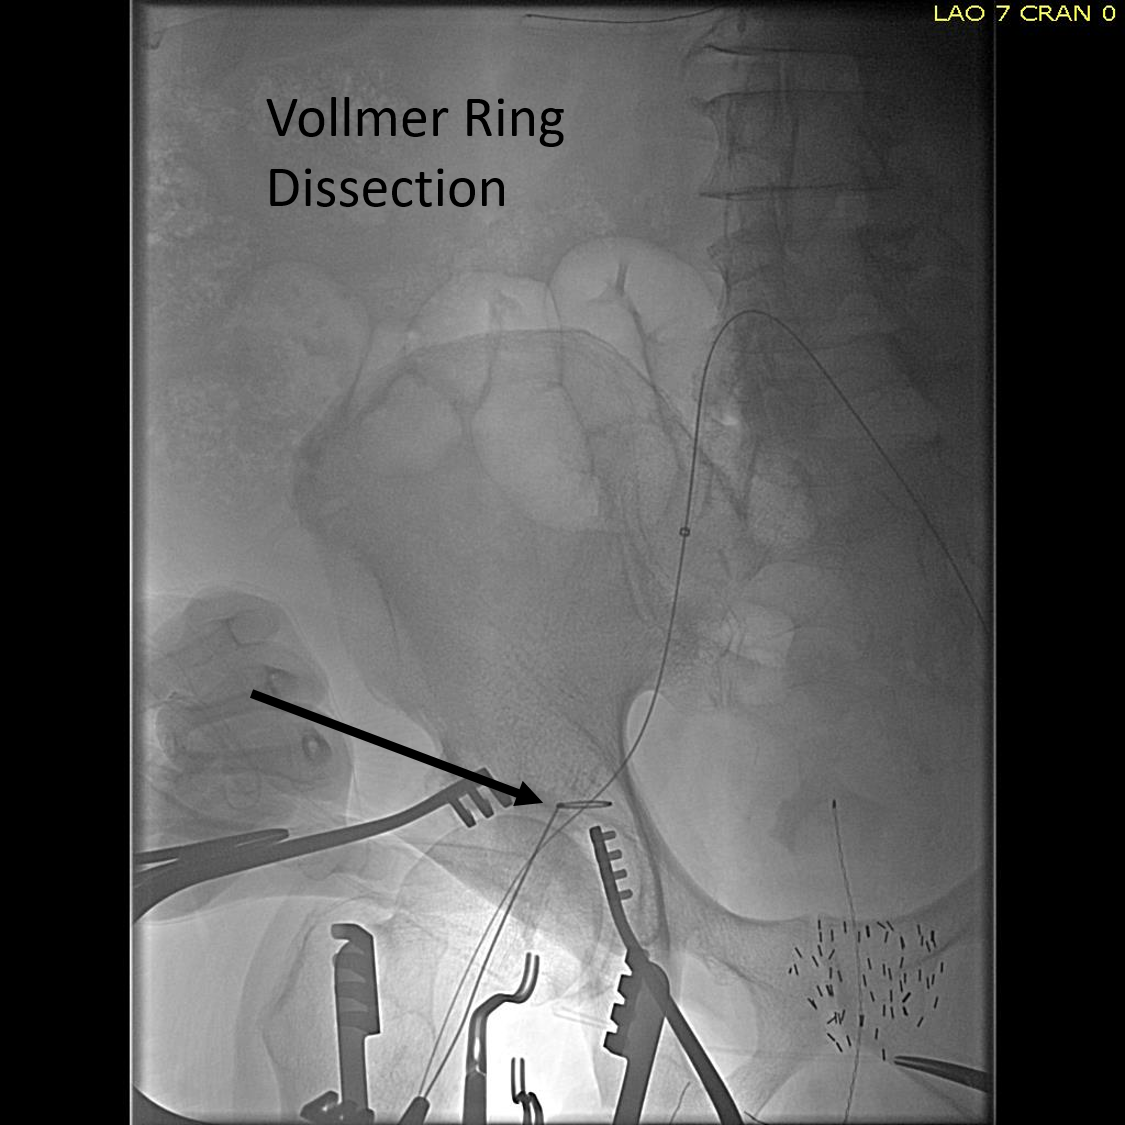

The common femoral endarterectomy is done from its distal most point and the Vollmer ring is used to mobilize the plaque. A Moll Ring Cutter (LeMaitre Vascular) is then used to cut the plaque.

Ring dissection.png